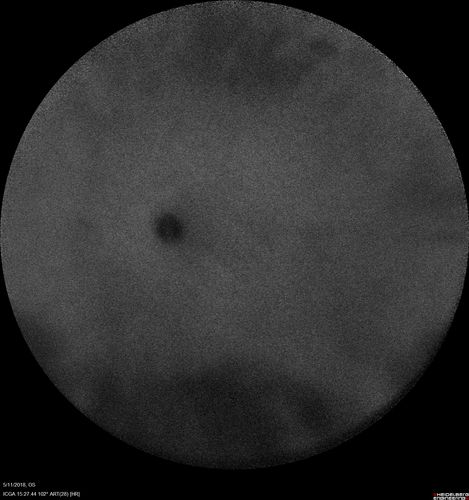

Multifocal Choroiditis - Pneumocystis - aspergillis - cryptococcus

31 year old male with anaplastic astrocytoma on chemotherapy with mild vision loss in the right eye.  LP did not reveal organism.  He was placed on a trial of anti-fungal medications and lost to follow-up